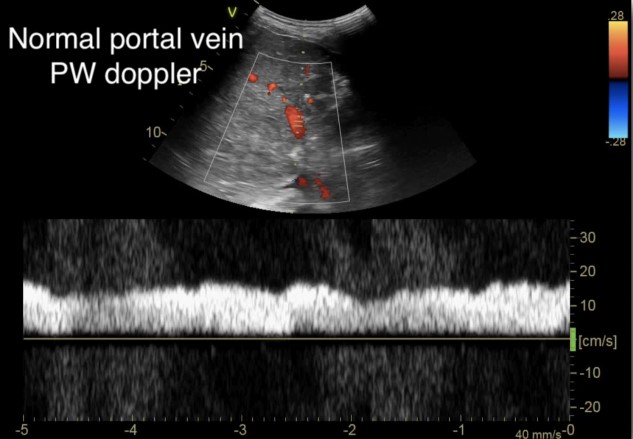

This is then repeated for the portal vein, allowing for adjustment of the image to obtain an optimal view (Figure 3). To help optimize measurements, the patient should perform a respiratory hold, as movement of the vessel itself during respirations limits the ability to obtain an accurate waveform.

Figure 3. Normal portal vein Doppler (continuous flow)10

(Reproduced with permission from Rola, Spiegel, and Haycock)

As we go past the hepatic sinusoids, into the portal venous system, the venous flow loses much of its pulsatility and instead maintains a more constant blood flow at normal levels of venous return. The normal portal venous waveform is continuous, as seen in Figure 3, and represents the flow of blood as it is buffered from the hepatic sinusoids. This unique aspect of the portal venous flow makes it more specific for increased venous congestion than measurement of the other veins, as it takes a greater amount of venous congestion to cause pulsatility in the portal vein. As venous congestion worsens, the portal vein will exhibit an increasing variation in the flow as the right atrial pressures increases and the hepatic sinusoids, which help regulate that flow, fail to compensate. This abnormal portal venous pulsatility is seen in Figure 7. As such, the portal vein waveform provides vital information about the ability of the liver itself to regulate venous flow and pulsatility.